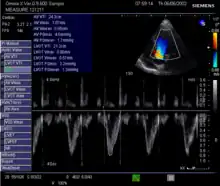

Doppler signal in the left ventricular outflow tract: Velocity Time Integral (VTI)

This method uses ultrasound and the Doppler effect to measure cardiac output. The blood velocity through the heart causes a Doppler shift in the frequency of the returning ultrasound waves. This shift can then be used to calculate flow velocity and volume, and effectively cardiac output, using the following equations:

where:

• CSA is the valve orifice cross sectional area,

• r is the valve radius, and,

• VTI is the velocity time integral of the trace of the Doppler flow profile.

Being non-invasive, accurate and inexpensive, Doppler ultrasound is a routine part of clinical ultrasound; it has high levels of reliability and reproducibility, and has been in clinical use since the 1960s.

Echocardiography is a non-invasive method of quantifying cardiac output using ultrasound. Two-dimensional (2D) ultrasound and Doppler measurements are used together to calculate cardiac output. 2D measurement of the diameter (d) of the aortic annulus allows calculation of the flow cross-sectional area (CSA), which is then multiplied by the VTI of the Doppler flow profile across the aortic valve to determine the flow volume per beat (stroke volume, SV). The result is then multiplied by the heart rate (HR) to obtain cardiac output. Although used in clinical medicine, it has a wide test-retest variability.[8] It is said to require extensive training and skill, but the exact steps needed to achieve clinically adequate precision have never been disclosed. 2D measurement of the aortic valve diameter is one source of noise; others are beat-to-beat variation in stroke volume and subtle differences in probe position. An alternative that is not necessarily more reproducible is the measurement of the pulmonary valve to calculate right-sided CO. Although it is in wide general use, the technique is time-consuming and is limited by the reproducibility of its component elements. In the manner used in clinical practice, precision of SV and CO is of the order of ±20%.